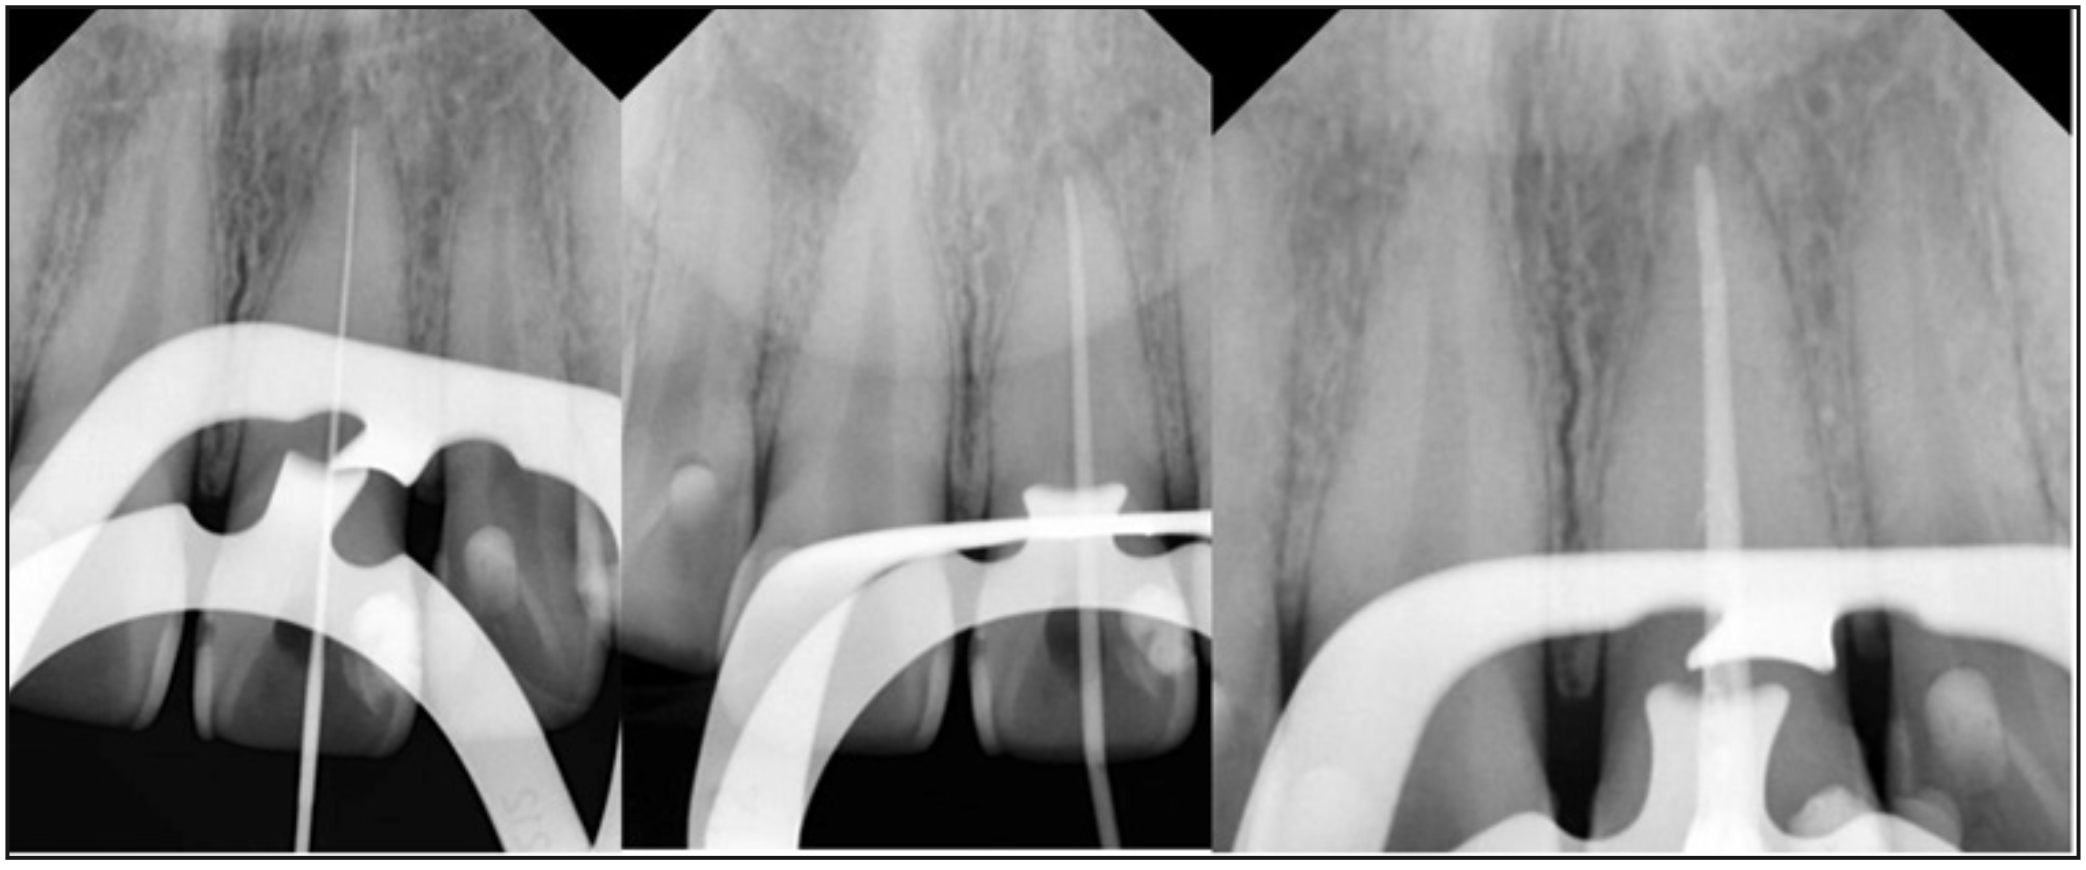

En una segunda sesión, el estudiante de pregrado, bajo supervisión del docente especialista, remueve la restauración provisoria de vidrio ionómero para visualizar el acceso guiado realizado anteriormente. Se realiza irrigación con hipoclorito de sodio al 5% (NaOCl) con jeringa de irrigación Monoject (Monoject TM, CardinalHealth Inc, Ohio). Se permeabiliza con una lima k de diámetro 10, y se determina la longitud de trabajo con localizador apical a 22 mm (Figura 3). Debido a las características del caso se decide utilizar instrumentación mecanizada con limas protaper next (protaper next, Dentsply Sirona, Charlotte) de medidas X1, X2, Y X3 respectivamente, y luego se termina de instrumentar con limas k 40 y 45, se deja medicación de hidróxido de calcio y se realiza una obturación provisoria.

En la siguiente sesión, la paciente llega asintomática por lo que se decide obturar, realizando un protocolo de irrigación final con NaOCl, luego EDTA al 17% con activación manual. Selección de cono maestro de gutapercha de diámetro 45 y conos accesorios 25, conometría (Figura 3) se utiliza cemento sellador AH Plus® (Dentsply Sirona, Charlotte) en la técnica de condensación lateral en frio, se realiza control de la obturación (Figura 3), y se realiza obturación provisoria de vidrio ionómero. Al control de la semana, la paciente se encontraba asintomática, y es derivada para la restauración definitiva del diente. Se cita a control a los 6 meses.

Figura 4. Conductometría, conometría y radiografía de control de obturación.